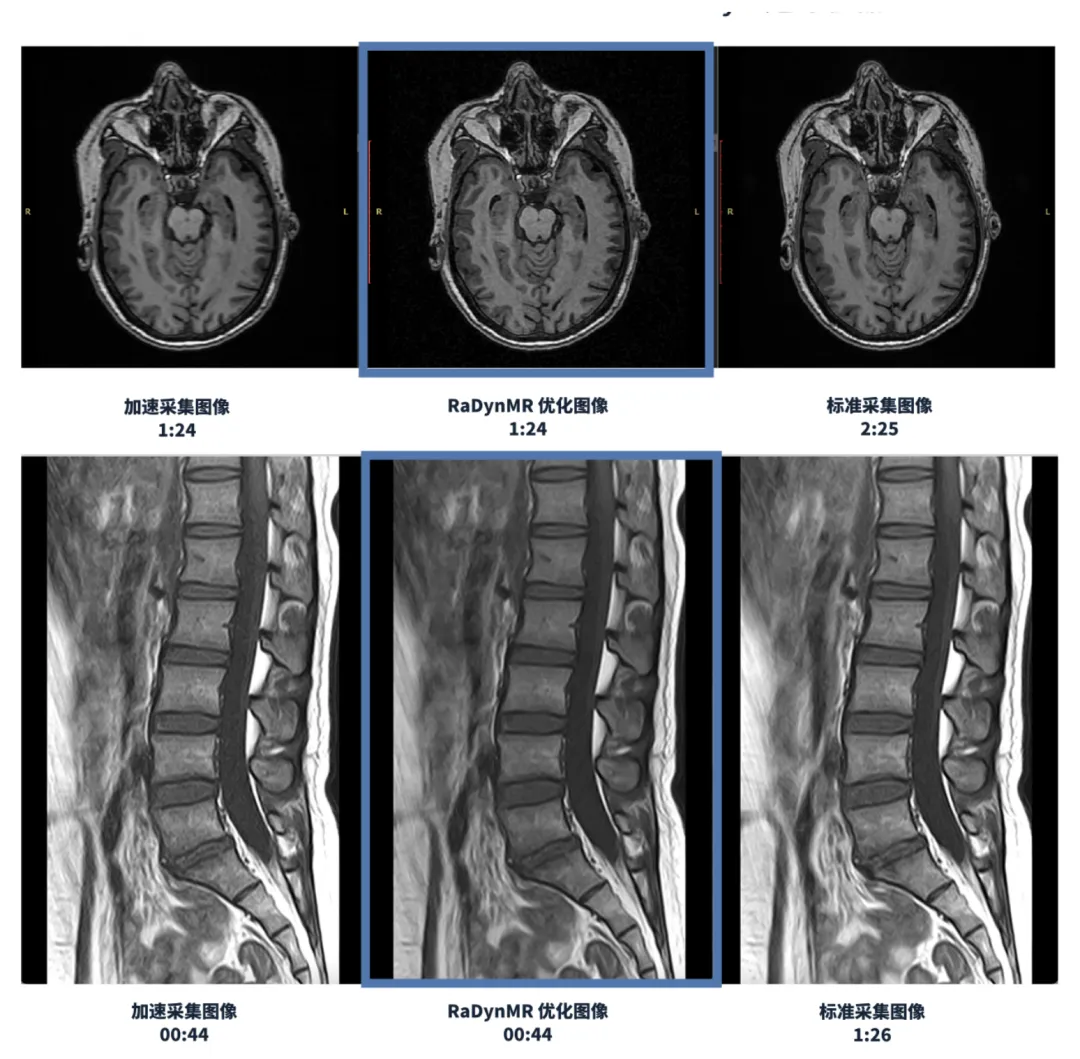

影动医疗是全影像 AI赋能方案供应商,致力于通过人工智能技术优化成像的上下游流程,解决传统影像中效率低、效果差、危害高的核心问题,使其更高效、更优质、更安全。

影动医疗技术应用